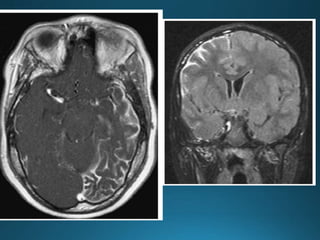

Giant cerebral aneurysms are ones that measure >25 mm in

greatest dimension.

Clinical presentation

Patients can present with symptoms and signs of mass effect

or subarachnoid haemorrhage 1,2.

Most commonly represent saccular cerebral aneurysms but

may also be fusiform or serpentine in morphology .They are

thought to develop via two pathways :

• internal elastic lamina de novo defect

• enlargement from a smaller aneurysm

MRI

On MRI also the patent and thrombosed aneurysm display different imaging

features:

T1

most of the patent aneurysm appears as flow void, or they may show

heterogeneous signal intensity

in thrombosed aneurysm appearance depends on the age of clot within the

lumen

T2

typically hypointense

laminated thrombus may show a hyperintense rim